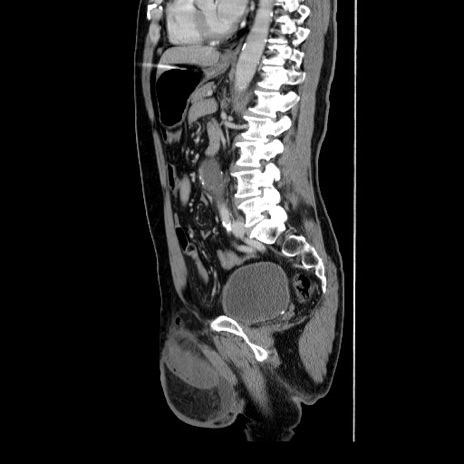

症例34(矢状断像)

【症例】60歳代 男性

【主訴】右鼠径部膨隆

【現病歴】1年程前より右鼠径部膨隆あり。自己にて還納可能だったため放置していた。3時間前より右鼠径部の脱出を認め、還納困難となり受診。

【身体所見】右鼠径部に小児頭大の膨隆あり。弾性硬であり、用手還納は困難。左鼠径部にも膨隆を認める。脱出はなし。